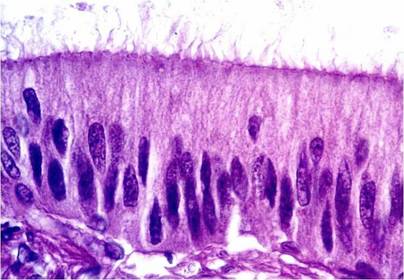

Tejido Epitelial de revestimiento, (epitelio intestinal). Prismático simple, microvellosidades en la zona apical

Tejido Epitelial de revestimiento, (epitelio intestinal)